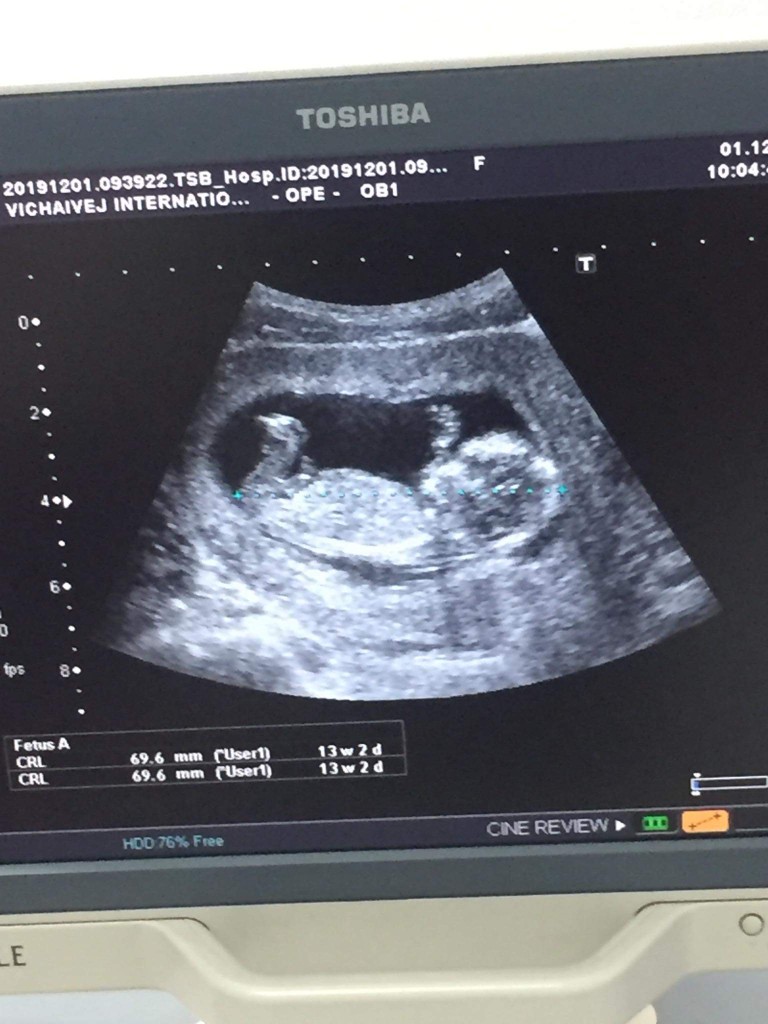

ไปอัลต้าซาวด์มาปกติเห็นแขนขาครบรึยังคะ แต่หมอก็บอกตอนนี้ครรภ์ยังน้อยอยู่(3เดือน) ไม่สามารถบอกได้ว่าครบ32 ไหม แอบกังวลนิดๆค่ะ แต่ก็คิดว่าเค้าคงยังไม่โตเหมือนที่หมอบอกมาคร่าวๆนั่นแหละ มีใครเคยซาวด์ตอนอายุครรภ์เท่ากันบ้างคะ ขอแชร์ประสบการณ์หน่อยค่ะ

ตอนนั้นซาว 13+5 ค่ะ ตอนนี้ 19+5 แล้วค่ะ

ตอนนี้14วีคคะ ตอนซาว13 .... 3เดือน